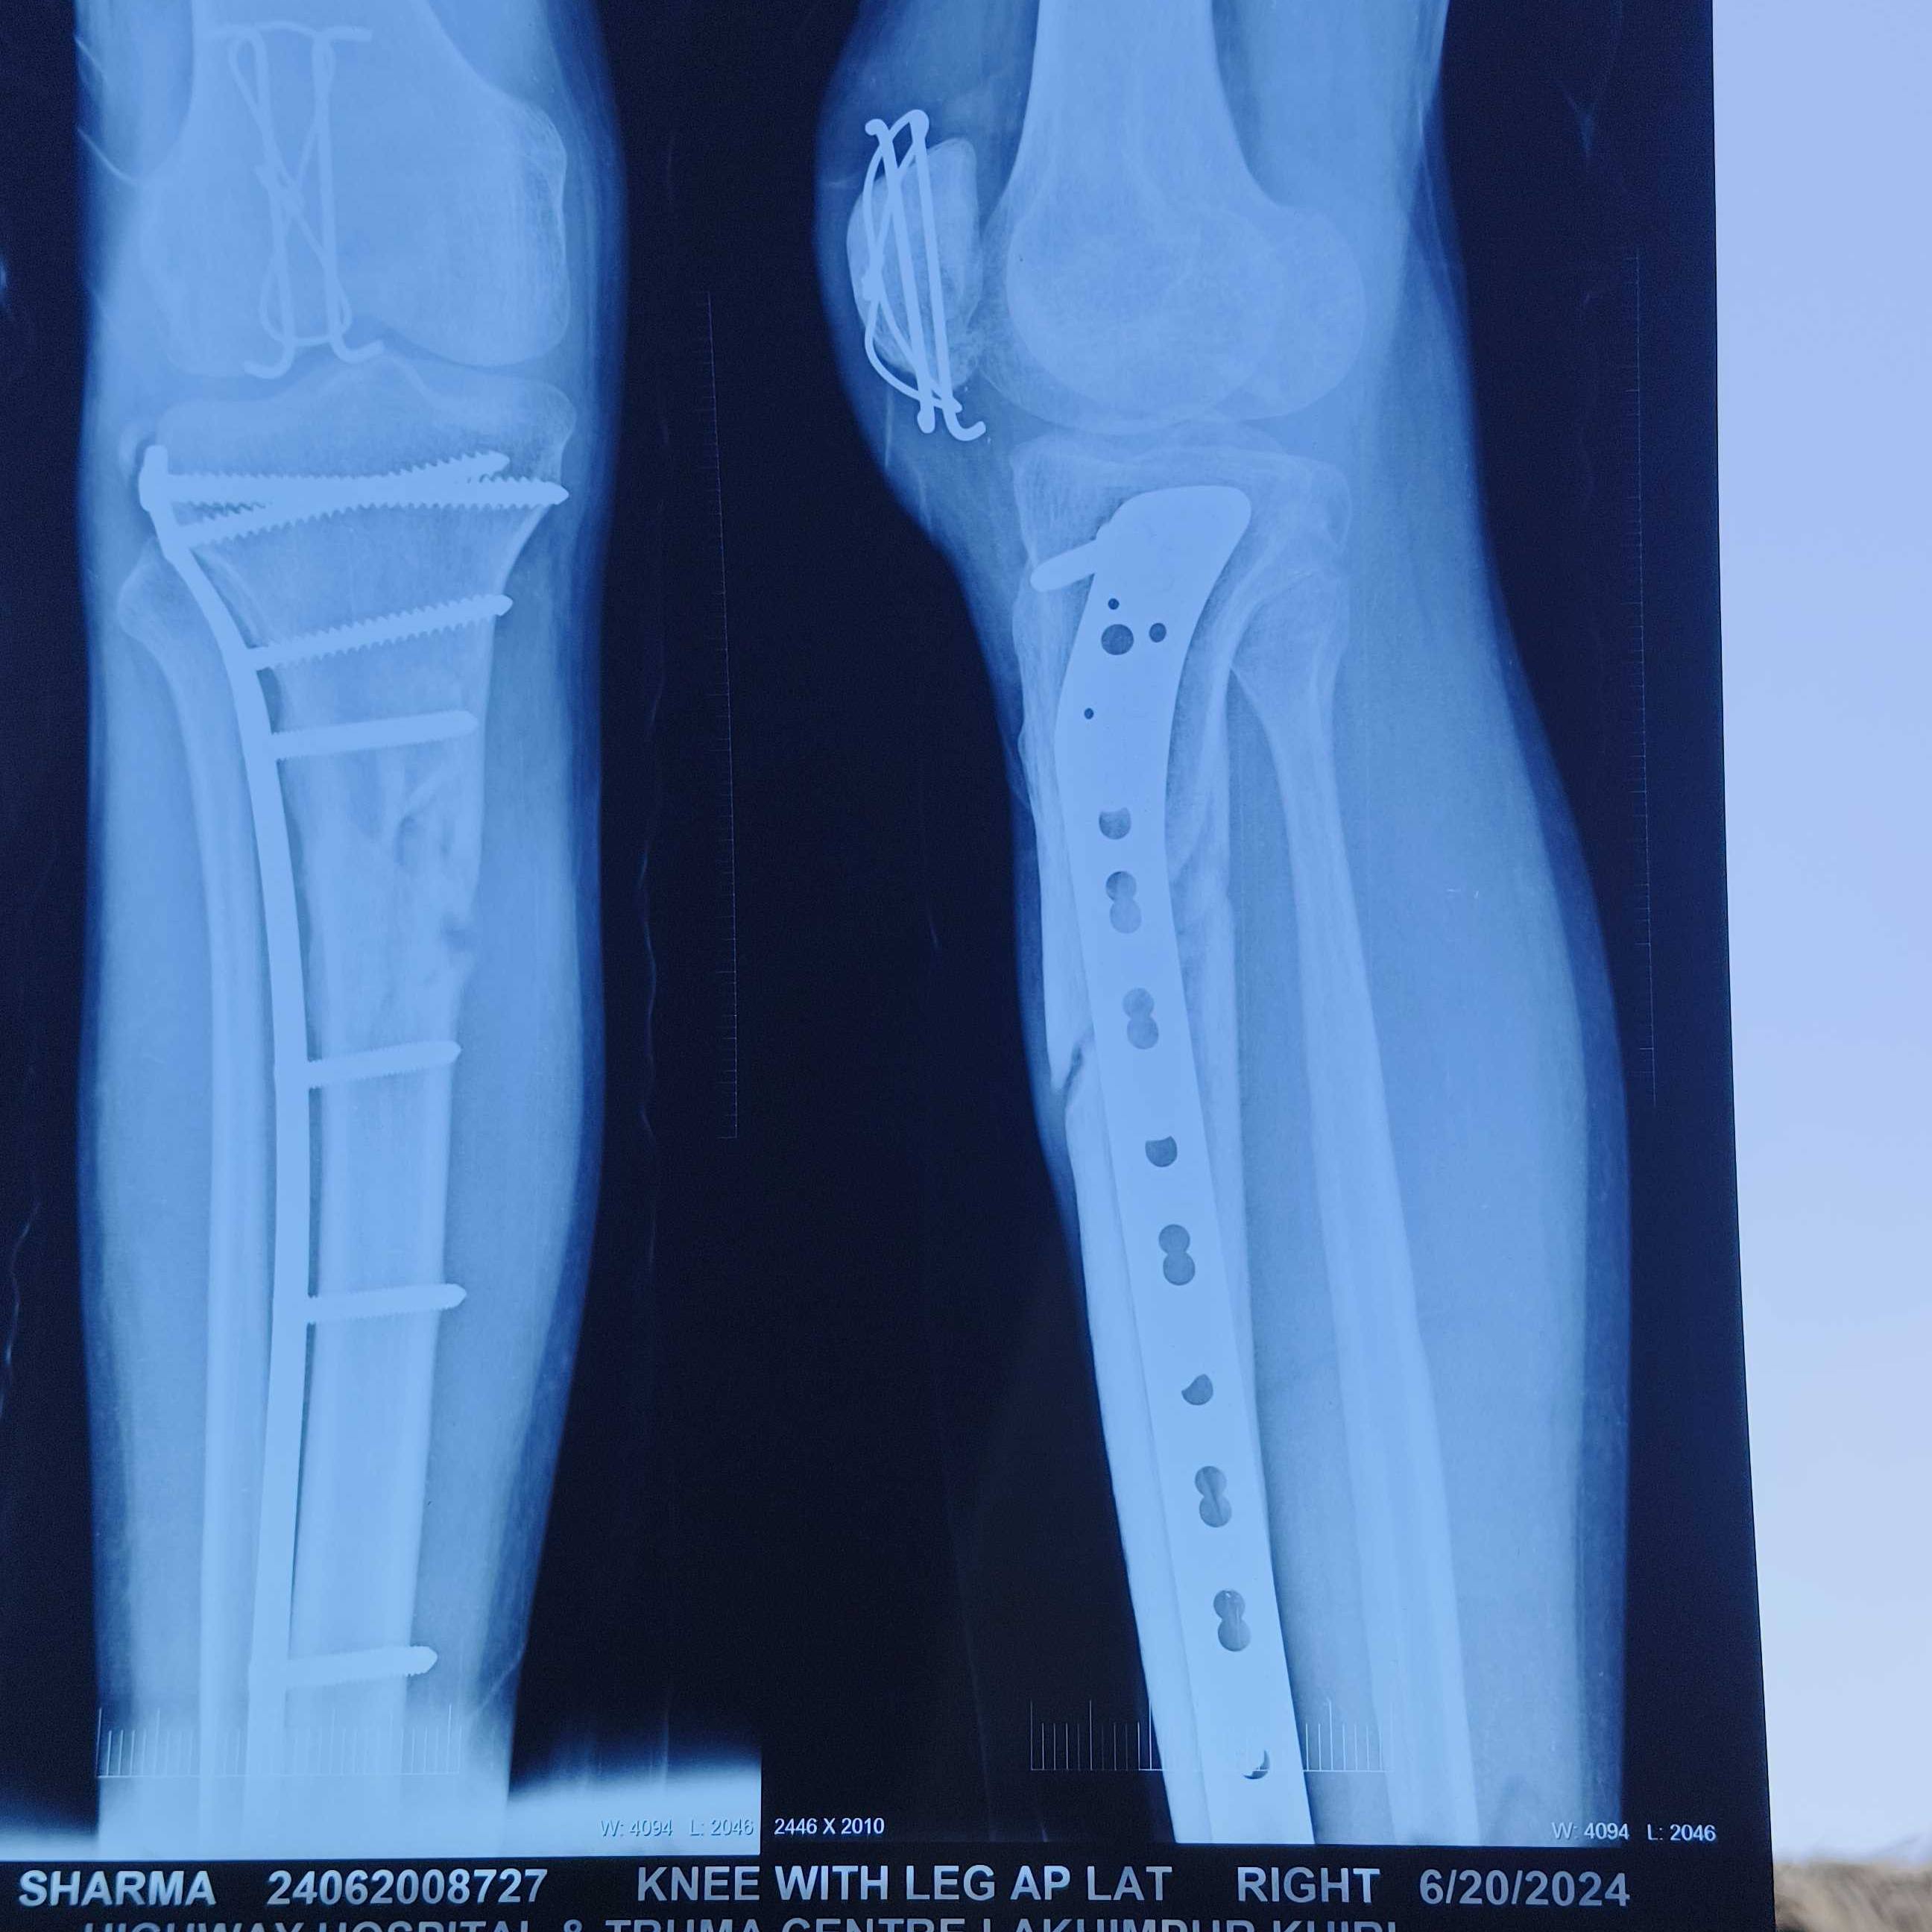

sir mera bike se accident hua tha jisme proximal tibia and patella fracture hua tha,jisko implant se fix kar diya gaya, lekin jab maine knee bending kee to tibia peeche ki taraf approx 8mm sag kar rahi thi jisse mujhe rehab karne me bahut problem Hui,aur jab mai full weight ke saath chalne laga to ghutne me lachak aane lagi ,ek saal hone ke baad bhi mai running nahi kar pa raha hu. lekin achhi bat ye hai ki knee bending 100,%hai sir implant SS ka tha jisse MRI bhi nahi ho sakti. sir please provide me solution. Arun Sharma 26Years.